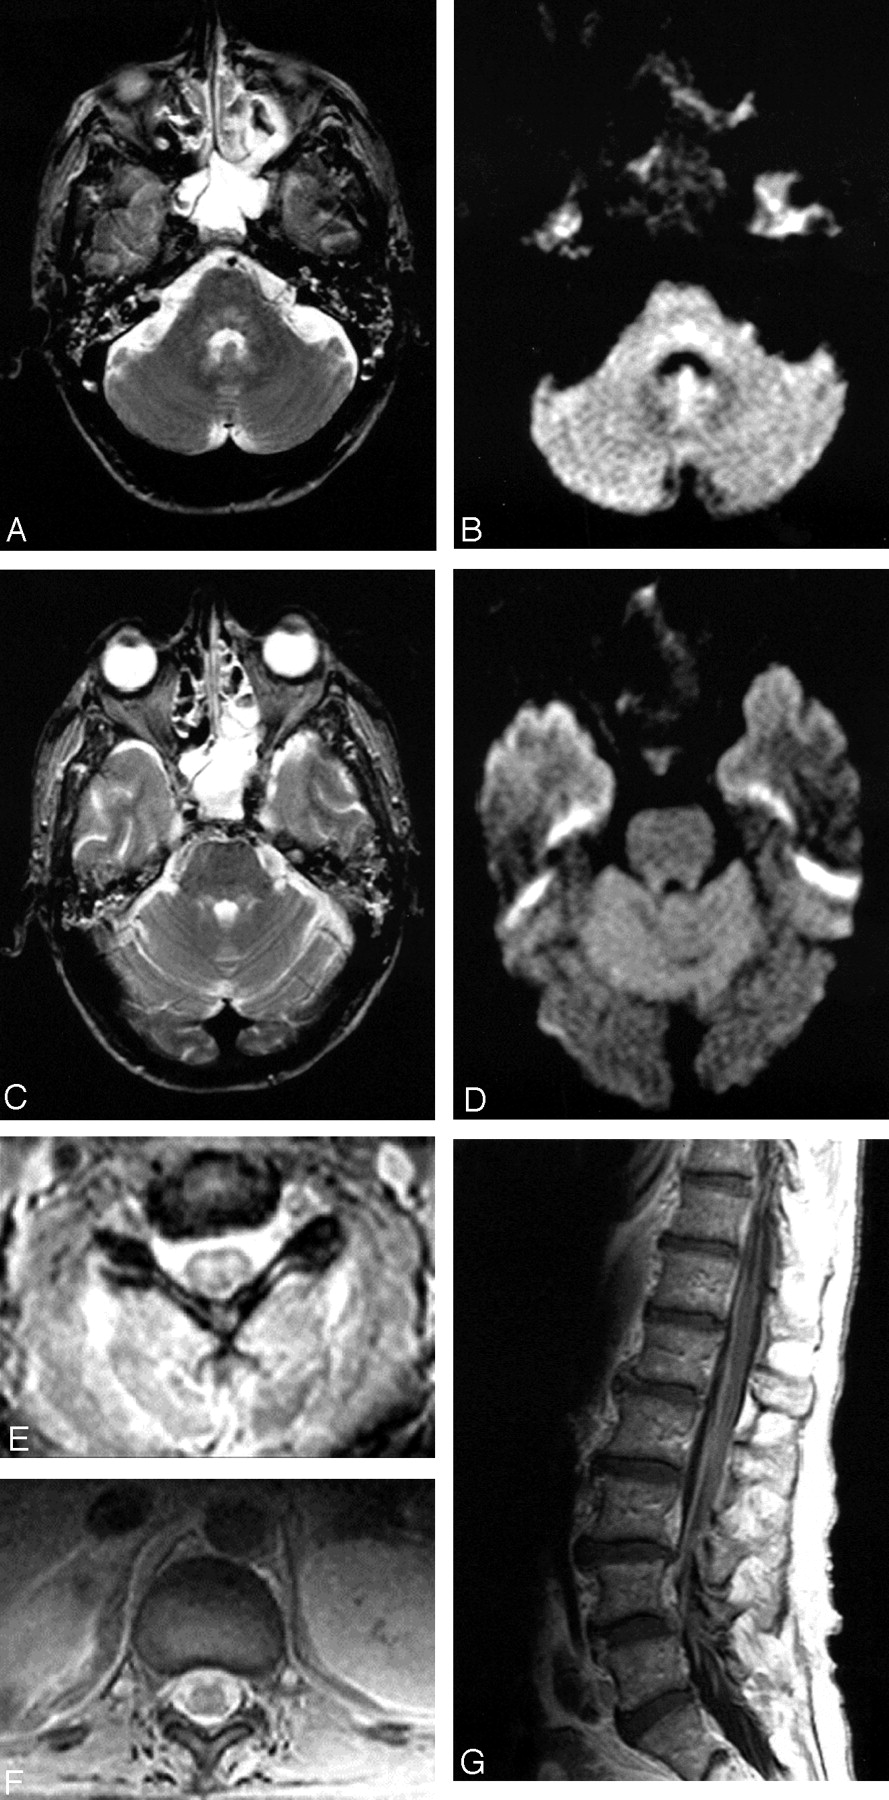

Patient 2, a 40-year-old man admitted with encephalitis and developed flaccid paralysis during hospitalization: axial FSE T2-weighted (A) and trace DW (B) images demonstrate increased signal intensity in the pontine tegmentum. Increased signal intensity was also seen in the superior cerebellar peduncles on FSE T2-weighted image (C), but not on the trace DW image (D). The patient was intubated at the time of imaging, which resulted in opacified sinuses and mastoid air cells. Axial GRE sequences through the cervical (E) and thoracic cord (F) show abnormal signal intensity in the gray matter with more pronounced involvement of the ventral horns. Postcontrast sagittal T1-weighted image (G) demonstrates enhancement of the cauda equina.

Midbrain involvement was noted in only 3 patients (Table 1); signal intensity abnormalities present in the cerebral peduncle and substantia nigra (Fig 2D, -J, and -K), as well as red nucleus (Fig 2N), are in accordance with prior case reports on Japanese and St. Louis encephalitides (13, 15). Involvements of the pontine tegmentum (Fig 1A and -B) and superior cerebellar peduncles (Fig 1C) were the first abnormalities to be noticed in one of the patients (2), who became ventilator dependent and progressed to develop flaccid paralysis. There were 4 patients who presented at some point with extremity weakness. All, with one exception (17), had MR imaging studies of the spine; abnormalities were seen in the gray matter and particularly the ventral horns in 2 of them, whereas enhancement of the conus medullaris and the cauda equina was seen in all 3. Prior reports have associated the flaccid paralysis with enhancement around the conus and along the cauda equina (2, 3). Anterior myelitis apparently contributes to the clinical picture as well (Figs 1E–G and 4A and -B). Abnormalities in the dentate nuclei, cerebellar white matter, and cortex were present in only one patient (Fig 2F, -G, -L, and -M) and are depicted on one of the follow-up MR imaging studies coinciding with newly developed “polio-like” symptoms. Unfortunately the patient’s spine was never imaged, so whether there were any additional findings of anterior myelitis and/or radiculitis remains unknown.